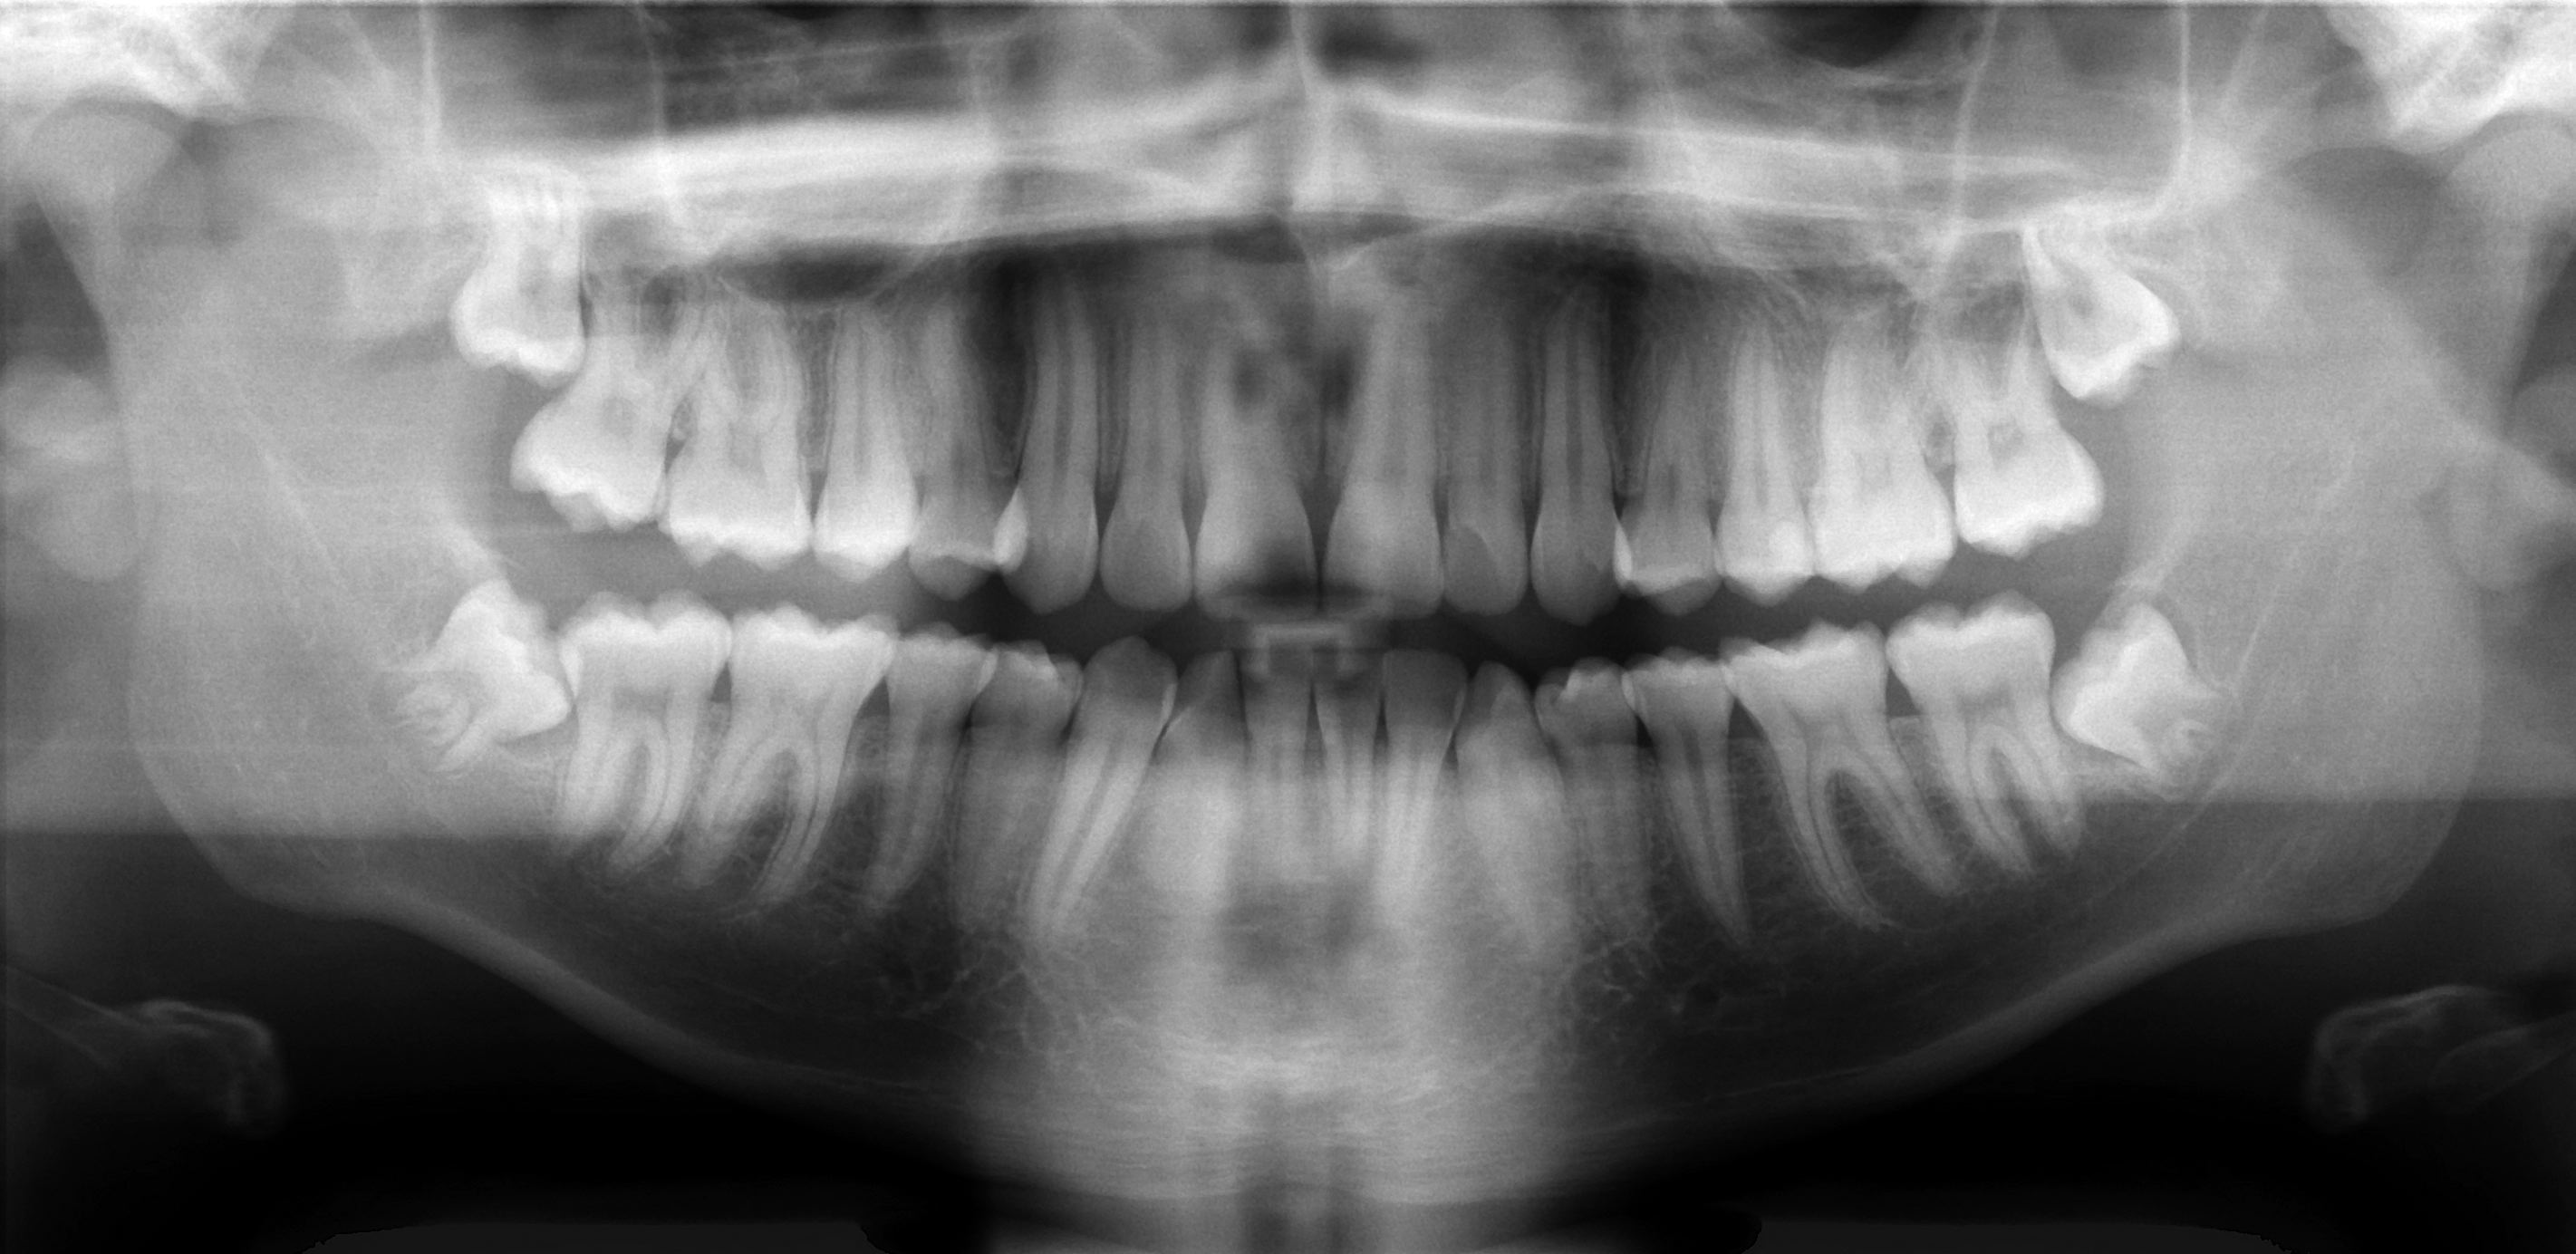

거대백악종을 진단하려면 턱과 치아의 모습을 보여주는 엑스레이 촬영이 필요하다. 파노라마 엑스레이와 [https://www.fda.gov/radiation-emitting-products/medical-x-ray-imaging/dental-cone-beam-computed-tomography#:~:text=computed%20tomography%20devices.-,Description,%2Dshaped%20X%2Dray%20beam. 콘빔 컴퓨터 단층 촬영(CBCT)] 등 다양한 유형의 엑스레이를 촬영할 수 있다. 구강외과 의사는 조직 검사를 위해 종양 조직을 채취하는 생검을 권할 수 있으며, 이는 진단 확정에 필요하다. 혈액 검사도 진단 확인을 위해 시행할 수 있다.

'''거대백악종'''과 관련된 증상이 나타나면 의료진의 진찰을 받는 것이 좋다. 도움을 줄 수 있는 의료진으로는 치과의사, 구강외과 의사, 구강악안면병리과 의사, 보철과 의사가 있다. 치과의사는 증상을 평가하고 환자를 적절한 전문의에게 의뢰하기 위해 진찰과 엑스레이 촬영을 할 수 있다. 구강외과 의사는 구강, 턱, 얼굴과 관련된 수술 절차를 전문으로 한다. 구강병리과 의사는 턱과 입과 관련된 질병을 진단하고 치료하기 위해 조직 샘플을 검사하여 진단에 도움을 줄 수 있다. 보철과 의사는 치아 결손을 보조할 수 있다. 이 의사들은 치과 보철물을 전문으로 한다. 환자를 '''거대백악종'''으로 진단하려면 종양을 식별하고 종양의 크기를 확인할 수 있도록 턱과 치아의 모습을 보여주는 엑스레이를 촬영해야 한다. 파노라마 엑스레이와 [https://www.fda.gov/radiation-emitting-products/medical-x-ray-imaging/dental-cone-beam-computed-tomography#:~:text=computed%20tomography%20devices.-,Description,%2Dshaped%20X%2Dray%20beam. 콘빔 컴퓨터 단층 촬영(CBCT)]과 같은 다양한 유형의 엑스레이를 촬영할 수 있다. 구강외과 의사는 조직 검사를 위해 종양에서 조직을 채취하기 위해 생검을 권할 수 있으며, 이는 진단을 확인하는 데 필요하다. 혈액 검사도 진단을 확인하기 위해 수행할 수 있다.